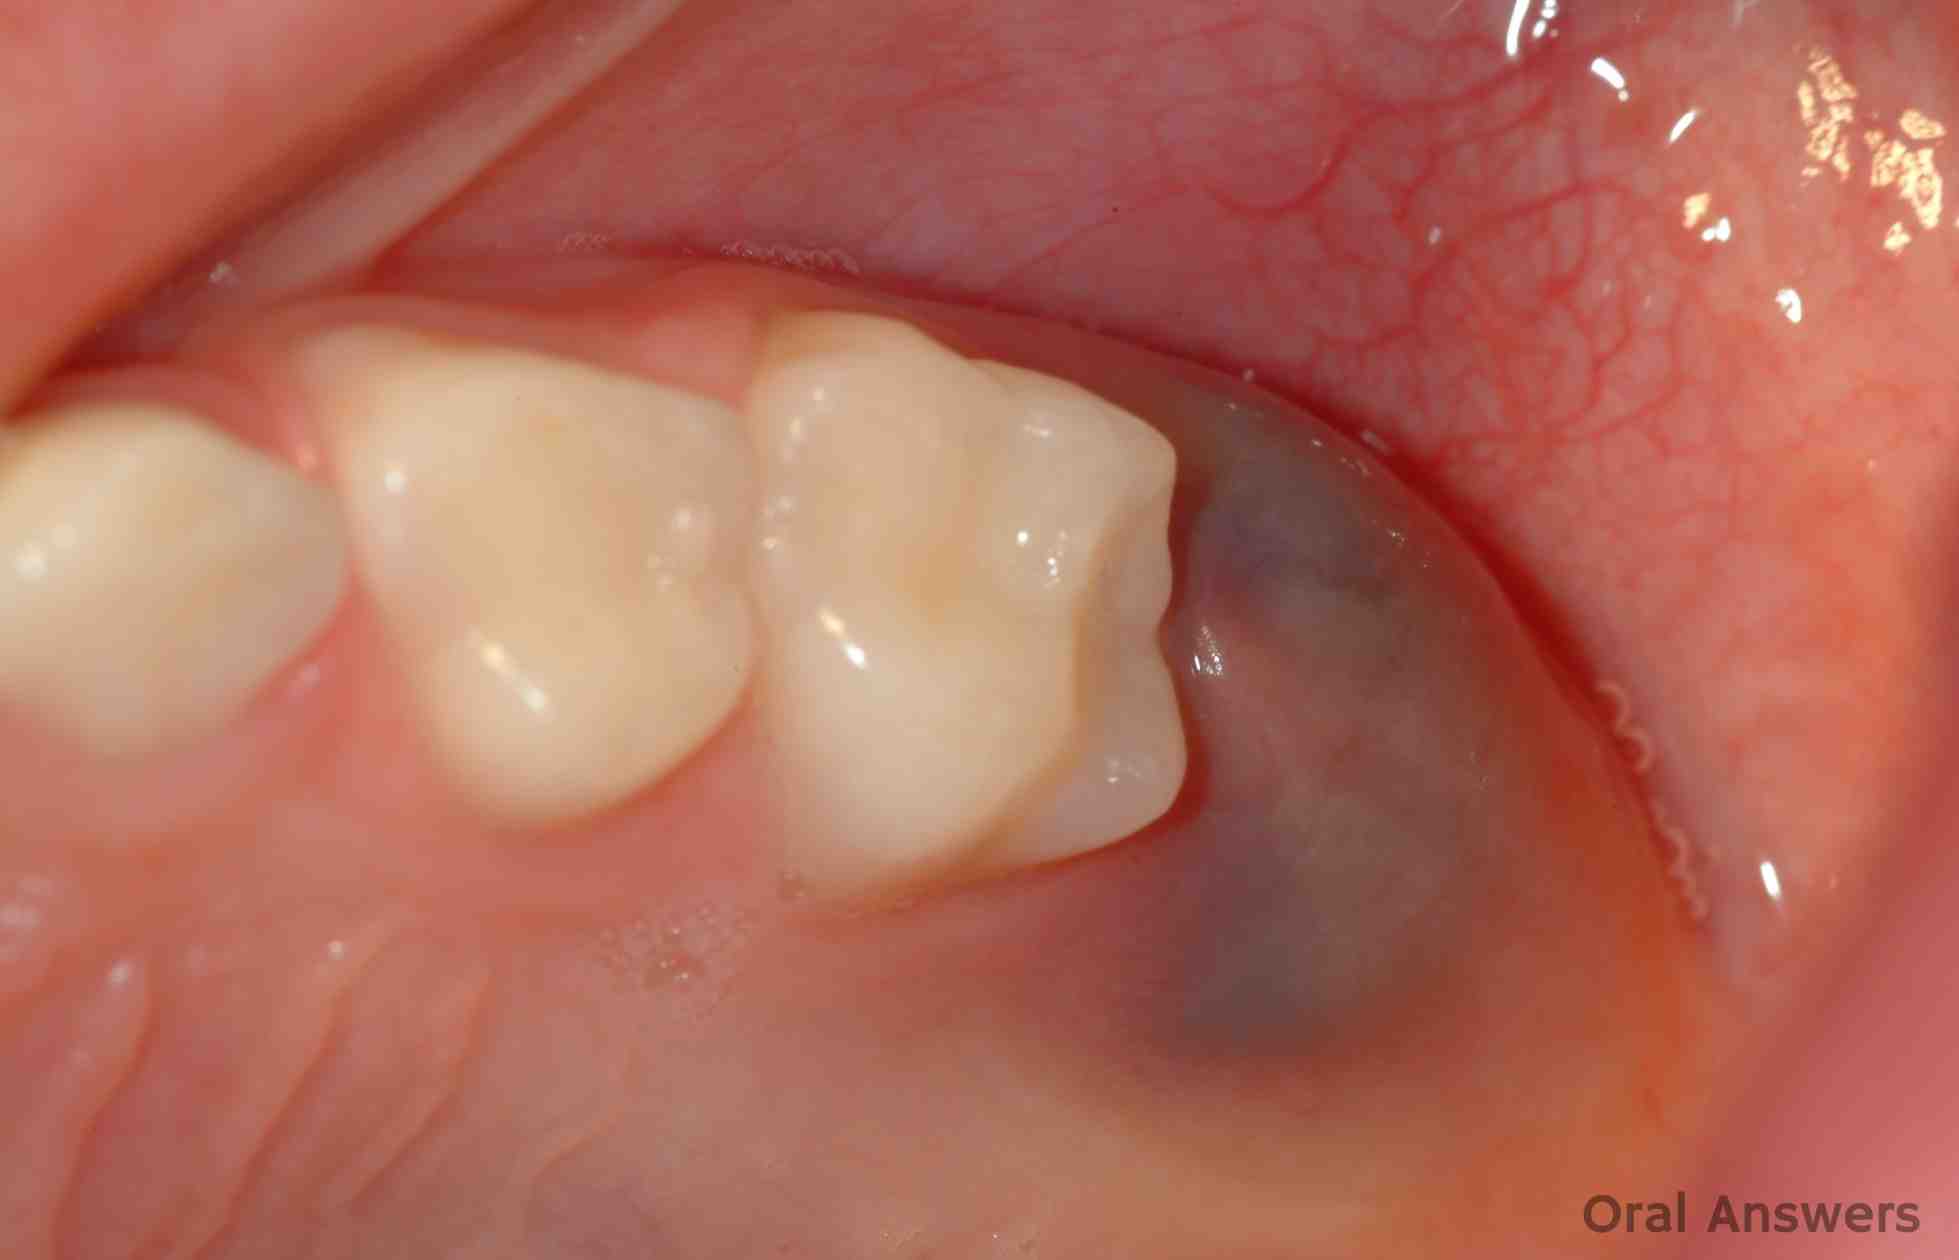

کیسی ددان

کیسی ددان -